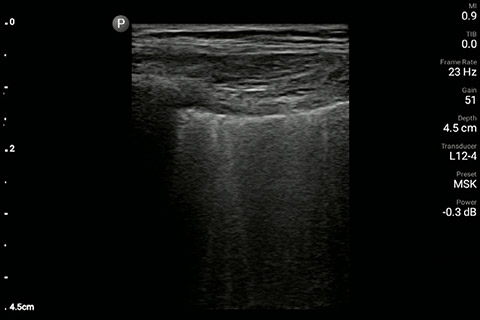

The patient had reduced LV systolic function without new or severe valvular pathology, a dilated, non-collapsing IVC, and diffuse B lines (left greater than right) on lung ultrasound imaging.

Lung image of the left chest